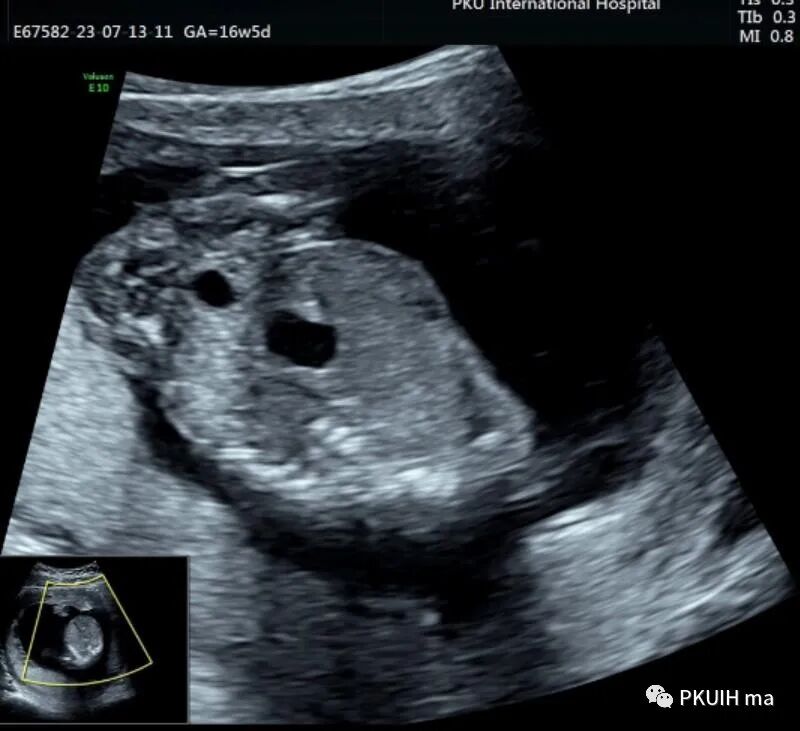

孕妇16周+5天常规超声检查发现腹部一囊性包块,如下图

胎儿中腹部见一囊性包块,大小约1.2x1.0x0.8cm,边界清,形态规则,内透声好。囊肿位于脊柱前方、胆囊后方、门静脉窦旁,与后肾接近

观察囊肿与肾、胃泡、膀胱均无相关。